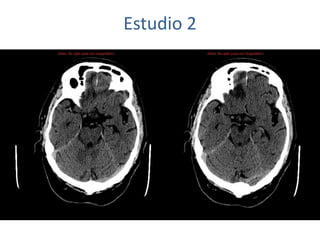

Estudio 2

• Estudio sin y con contraste, con reconstrucciones sagitales y coronales

del estudio con contraste.

Se observa una lesión ocupante de espacio en lóbulo frontal derecho que

presenta un tamaño de 18 x 32 x 22 mm (cc x ap x tr), bilobulada, no del

todo bien delimitada, con realce en anillo irregular, con hipocaptación

central, probablemente por necrosis, y asociada a un extenso edema

vasogénico con efecto masa tanto sobre los surcos de la convexidad

como sobre la cisterna insular, el sistema ventricular y la línea media,

esta última con un desplazamiento de 5 mm a la altura del septo

interventricular.

No se aprecian otras lesiones focales intra o extraaxiales de significación

patológica.

Habría que considerar como primera posibilidad que se tratase de una

lesión metastásica, por bien un tumor primario, aunque no se puede

descartar otras opciones, sin imprescindible correlación con la clínica y

con sus antecedentes.